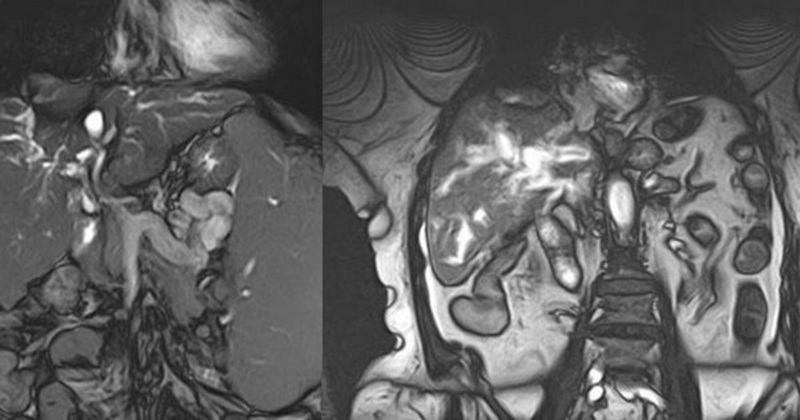

Магнитно-резонансная томография забрюшинного пространства – это высокоточное исследование, которое широко используется для выявления различных заболеваний, патологий в области брюшинных органов. Оно предоставляет детальные изображения мягких тканей, что делает его необходимым для диагностики, планирования лечения.

МРТ забрюшинного пространства является чрезвычайно чувствительным методом для выявления опухолей, новообразований в области живота. Его используют для дифференциальной диагностики, определения характера объекта, его распределения в окружающих тканях.

МР-томография детально исследует почки, мочевыделительную систему в целом. Этот метод широко применяется для выявления кист, злокачественных новообразований, камней, других аномалий, которые влияют на функцию почек, мочевыводящих путей.